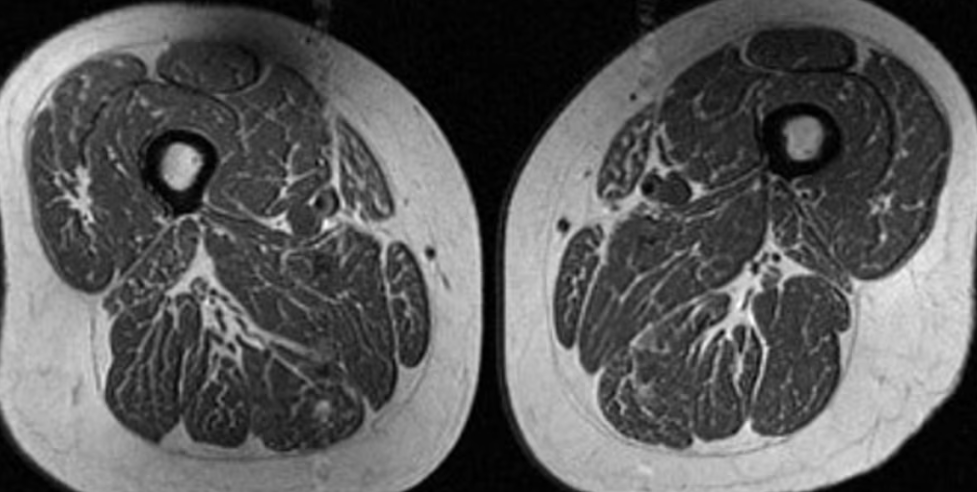

Imazhi duket si një copë mishi shumë e “mermerizuar”, që të kujton një biftek me shumë fijëza yndyre të shpërndara imët. Por kjo nuk është darkë. Është një skanim MRI i kofshës së një gruaje 62-vjeçare që merrte 87% të kalorive të saj vjetore nga ushqime ultra të përpunuara.

“Kjo pjesëmarrëse ushqehej kryesisht me drithëra të ftohta, çokollata ose karamele, pije të gazuara të zakonshme ose pije të ëmbla në shishe,” tha Dr. Zehra Akkaya, studiuese dhe konsulente në grupin e kërkimit për imazherinë muskuloskeletore në Universitetin e Kalifornisë, San Francisko.

Vijat e fshehura të yndyrës mes dhe brenda fibrave muskulore mund të sinjalizojnë probleme serioze shëndetësore, tha Akkaya, autorja kryesore e një studimi të ri që analizoi si ndikojnë ushqimet ultra të përpunuara në yndyrën brenda muskujve tek njerëzit në rrezik për osteoartrit të gjurit. Ushqimet ultra të përpunuara janë lidhur me shtim në peshë dhe obezitet, si dhe me zhvillimin e sëmundjeve kronike si kanceri, sëmundjet kardiovaskulare, diabeti i tipit 2 dhe depresioni. Këto ushqime mund të shkurtojnë edhe jetën.

Një grua tjetër 61-vjeçare në studim kishte gjithashtu yndyrë të shpërndarë në muskujt e kofshës, por jo aq të theksuar. Rreth 29% e dietës së saj përbëhej nga ushqime ultra të përpunuara.